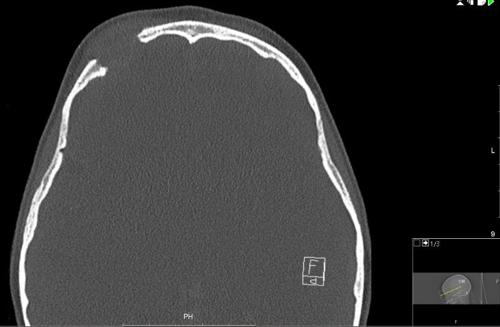

The CT scan (Fig 3) showed a destructive lesion superior to the right globe with destruction of right frontal bone and also the supra-orbital ridge. There was a solid material of intermediate density with well-defined margins bulging into the eyelid. Bony views showed a very well defined ‘punched out’ lesion well away from the sinuses. Further evaluation with an MRI was suggested to characterise the lesion.

Fig 3.